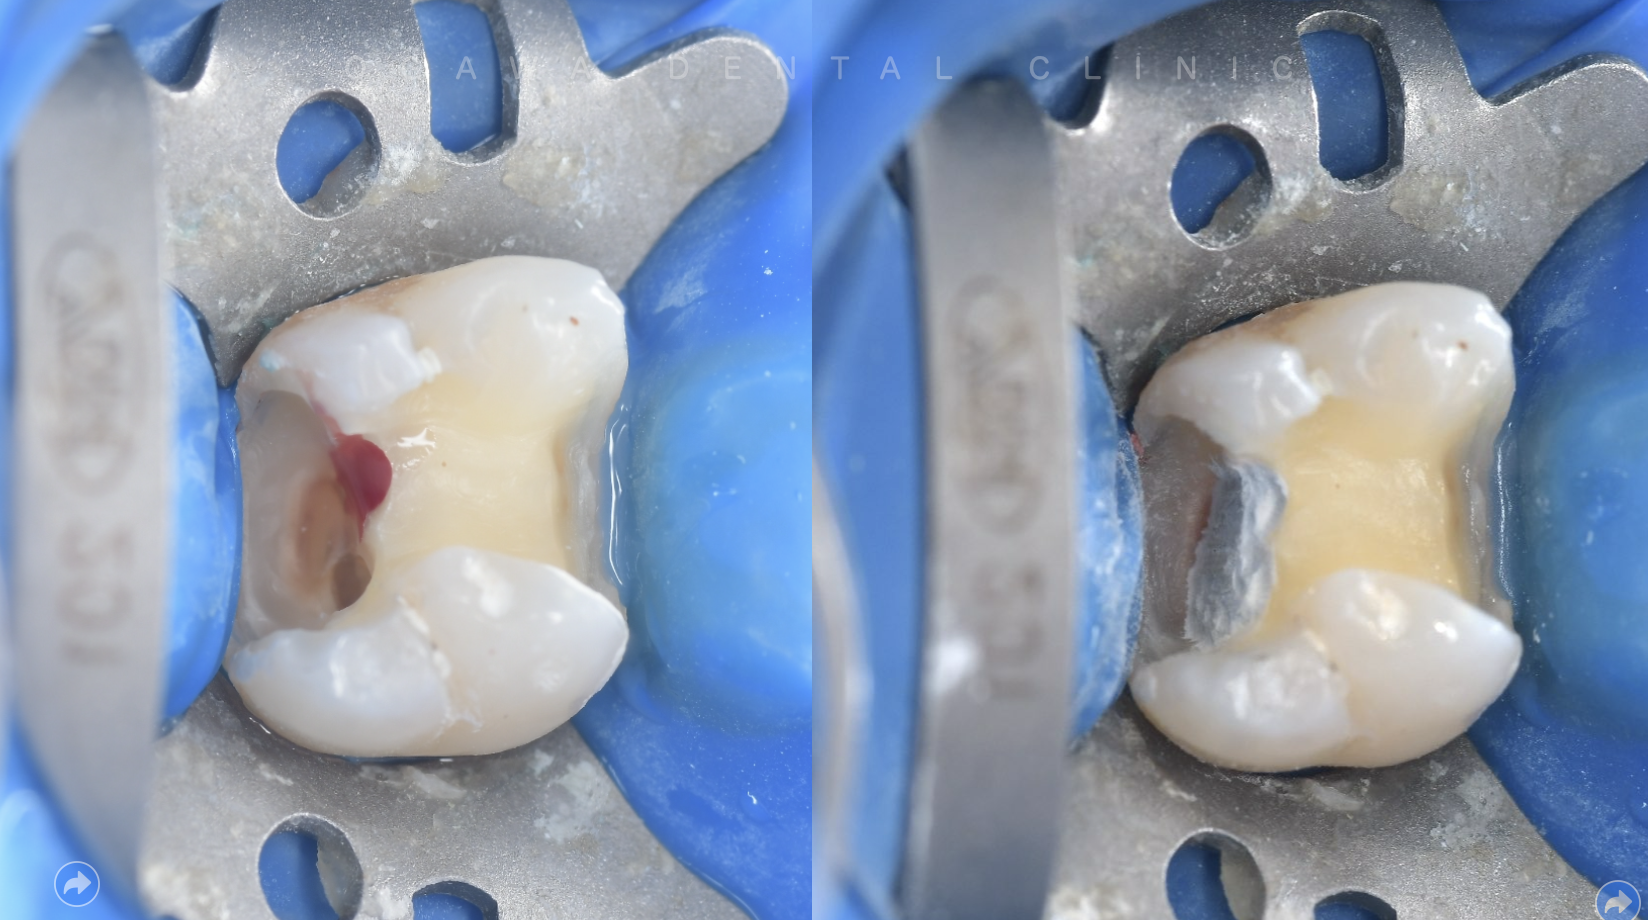

ラバーダム というゴムのシートで治療部位を覆い、清潔な環境を確保

治療後は、再度感染しないように精密な詰め物で修復